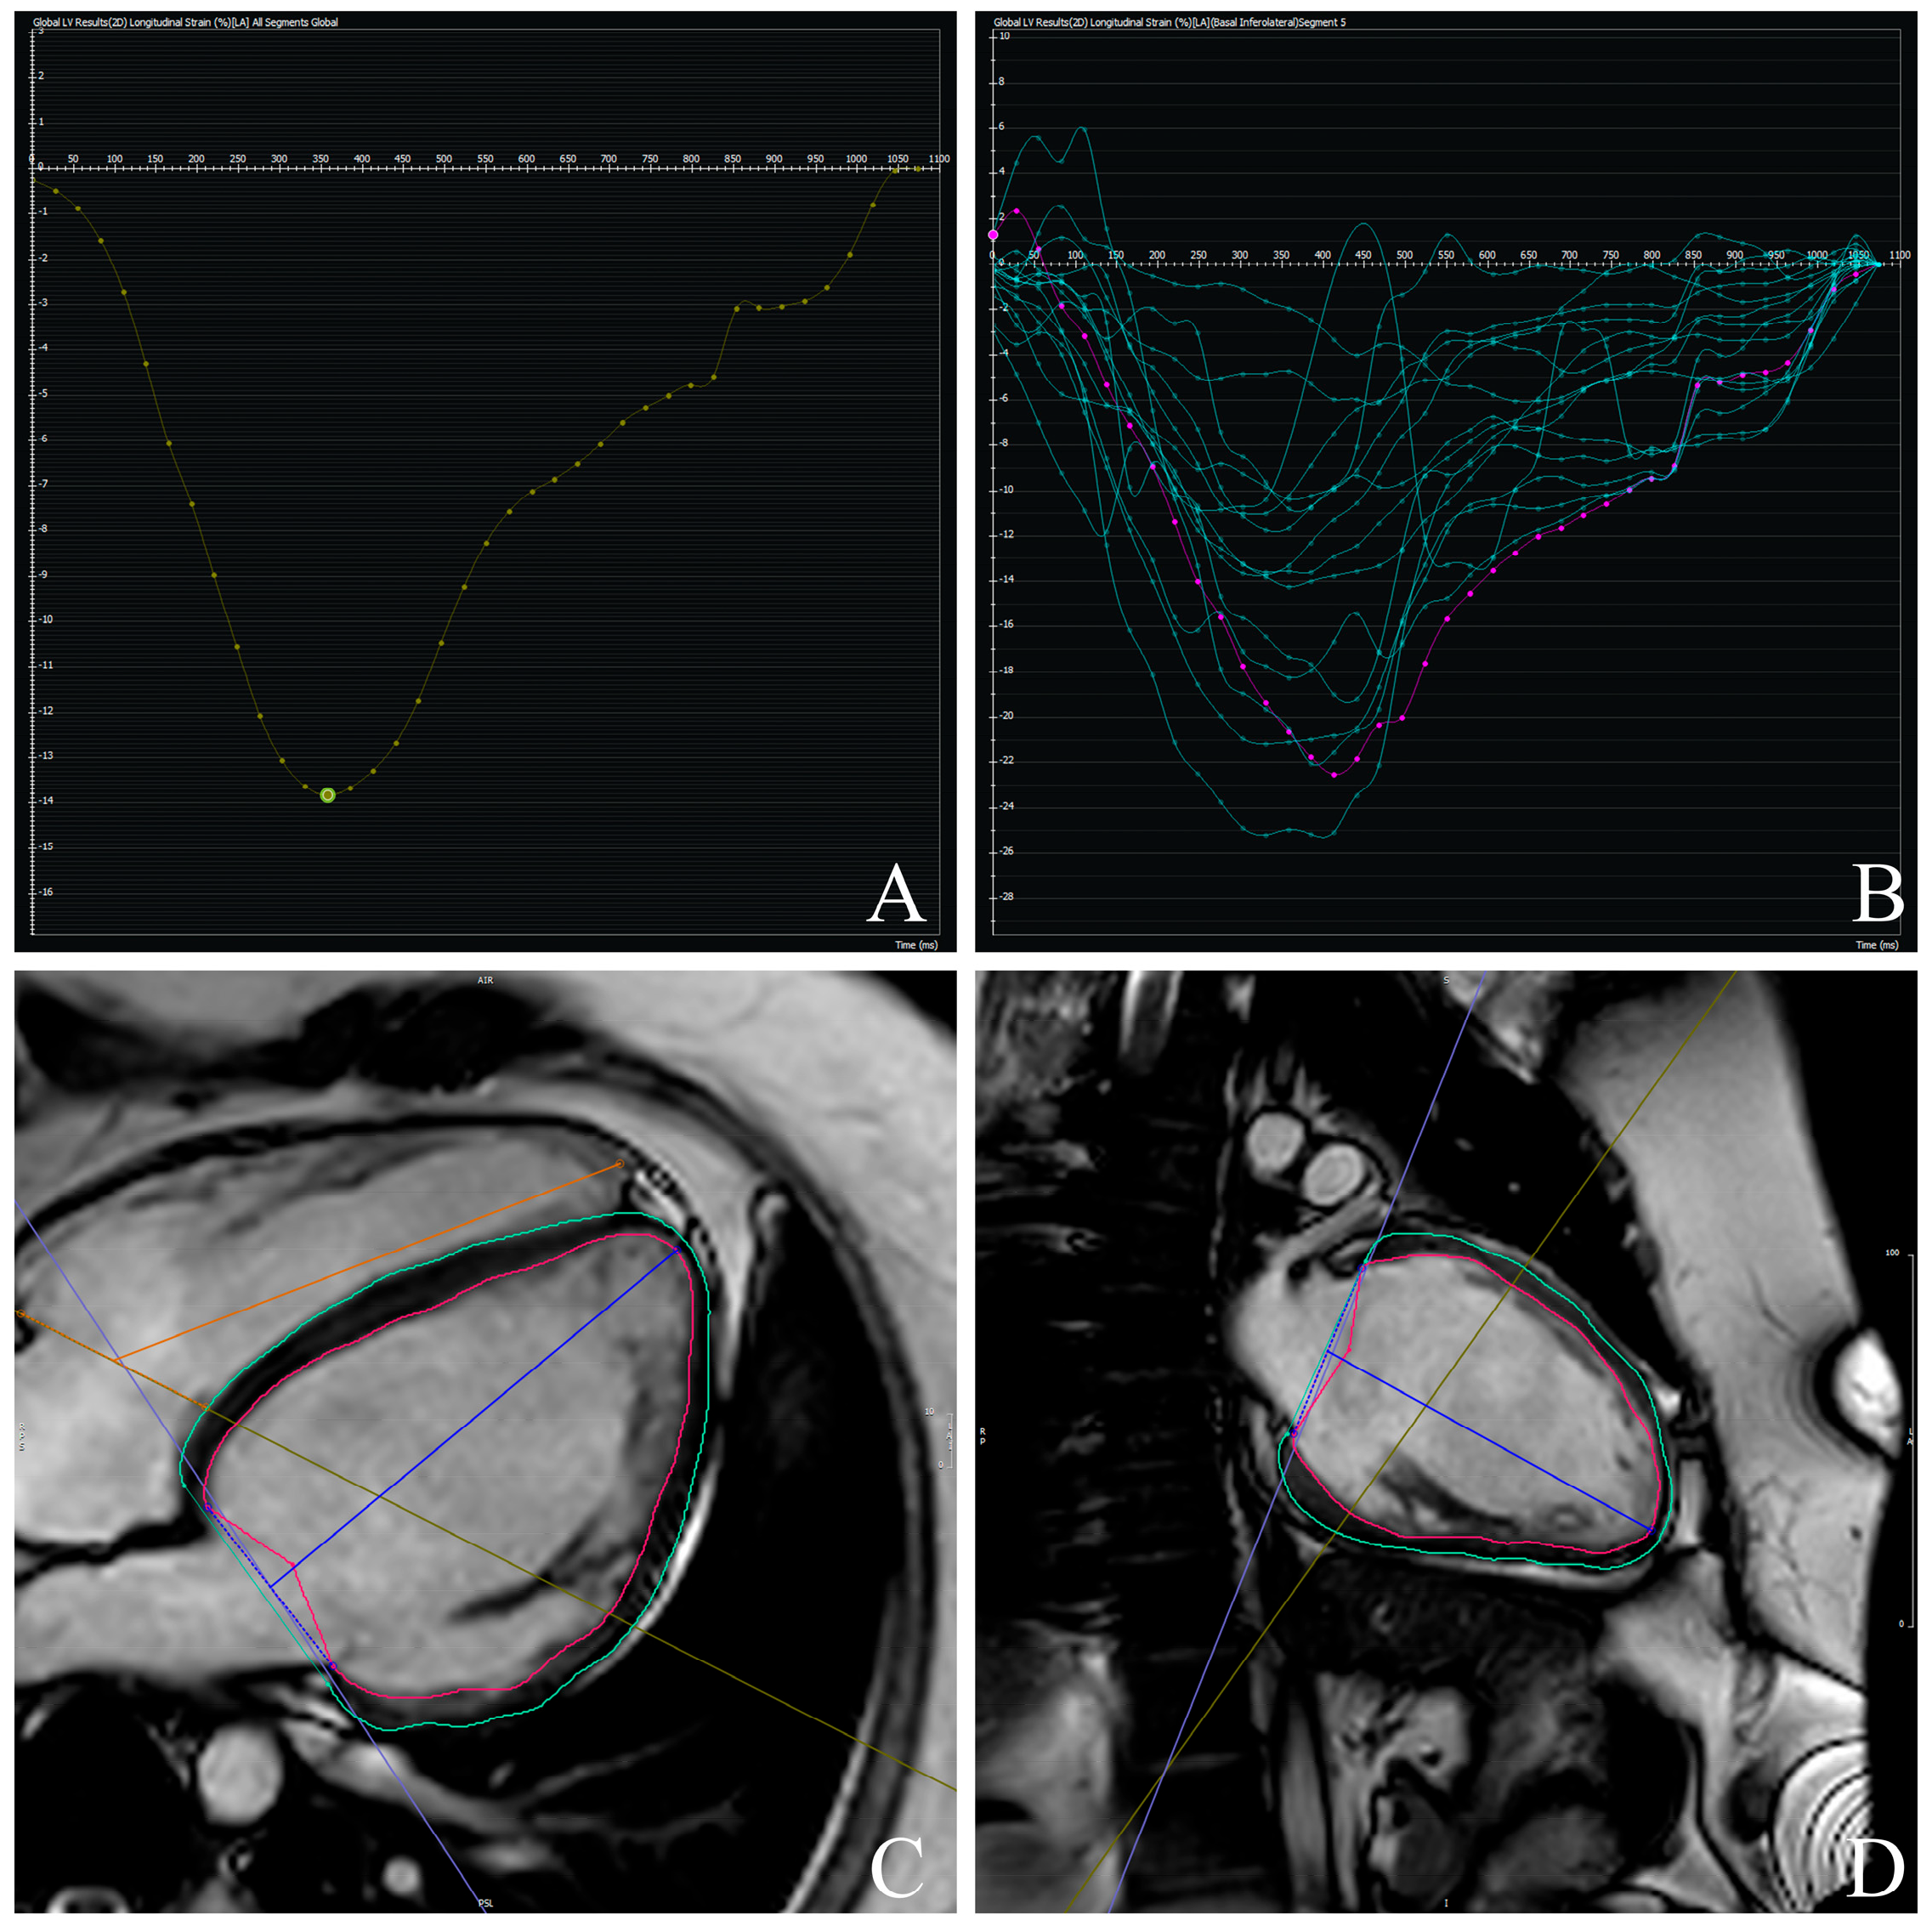

3.3. Prognostic Value of CMR-Derived GLS

| −9.2 (4.5) | −19.7 (1.3) | <0.001 |

| GLS, % | −9.5 (4.8) | −7.7 (2.1) | 1.21 (1.01–1.44) | 0.034 | 1.09 (1.01–1.61) | <0.01 |